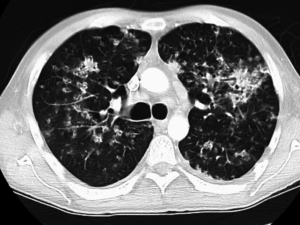

ct image pulmonary TB

CT image of pulmonary TB (James Heilman, Wikimedia Commons)